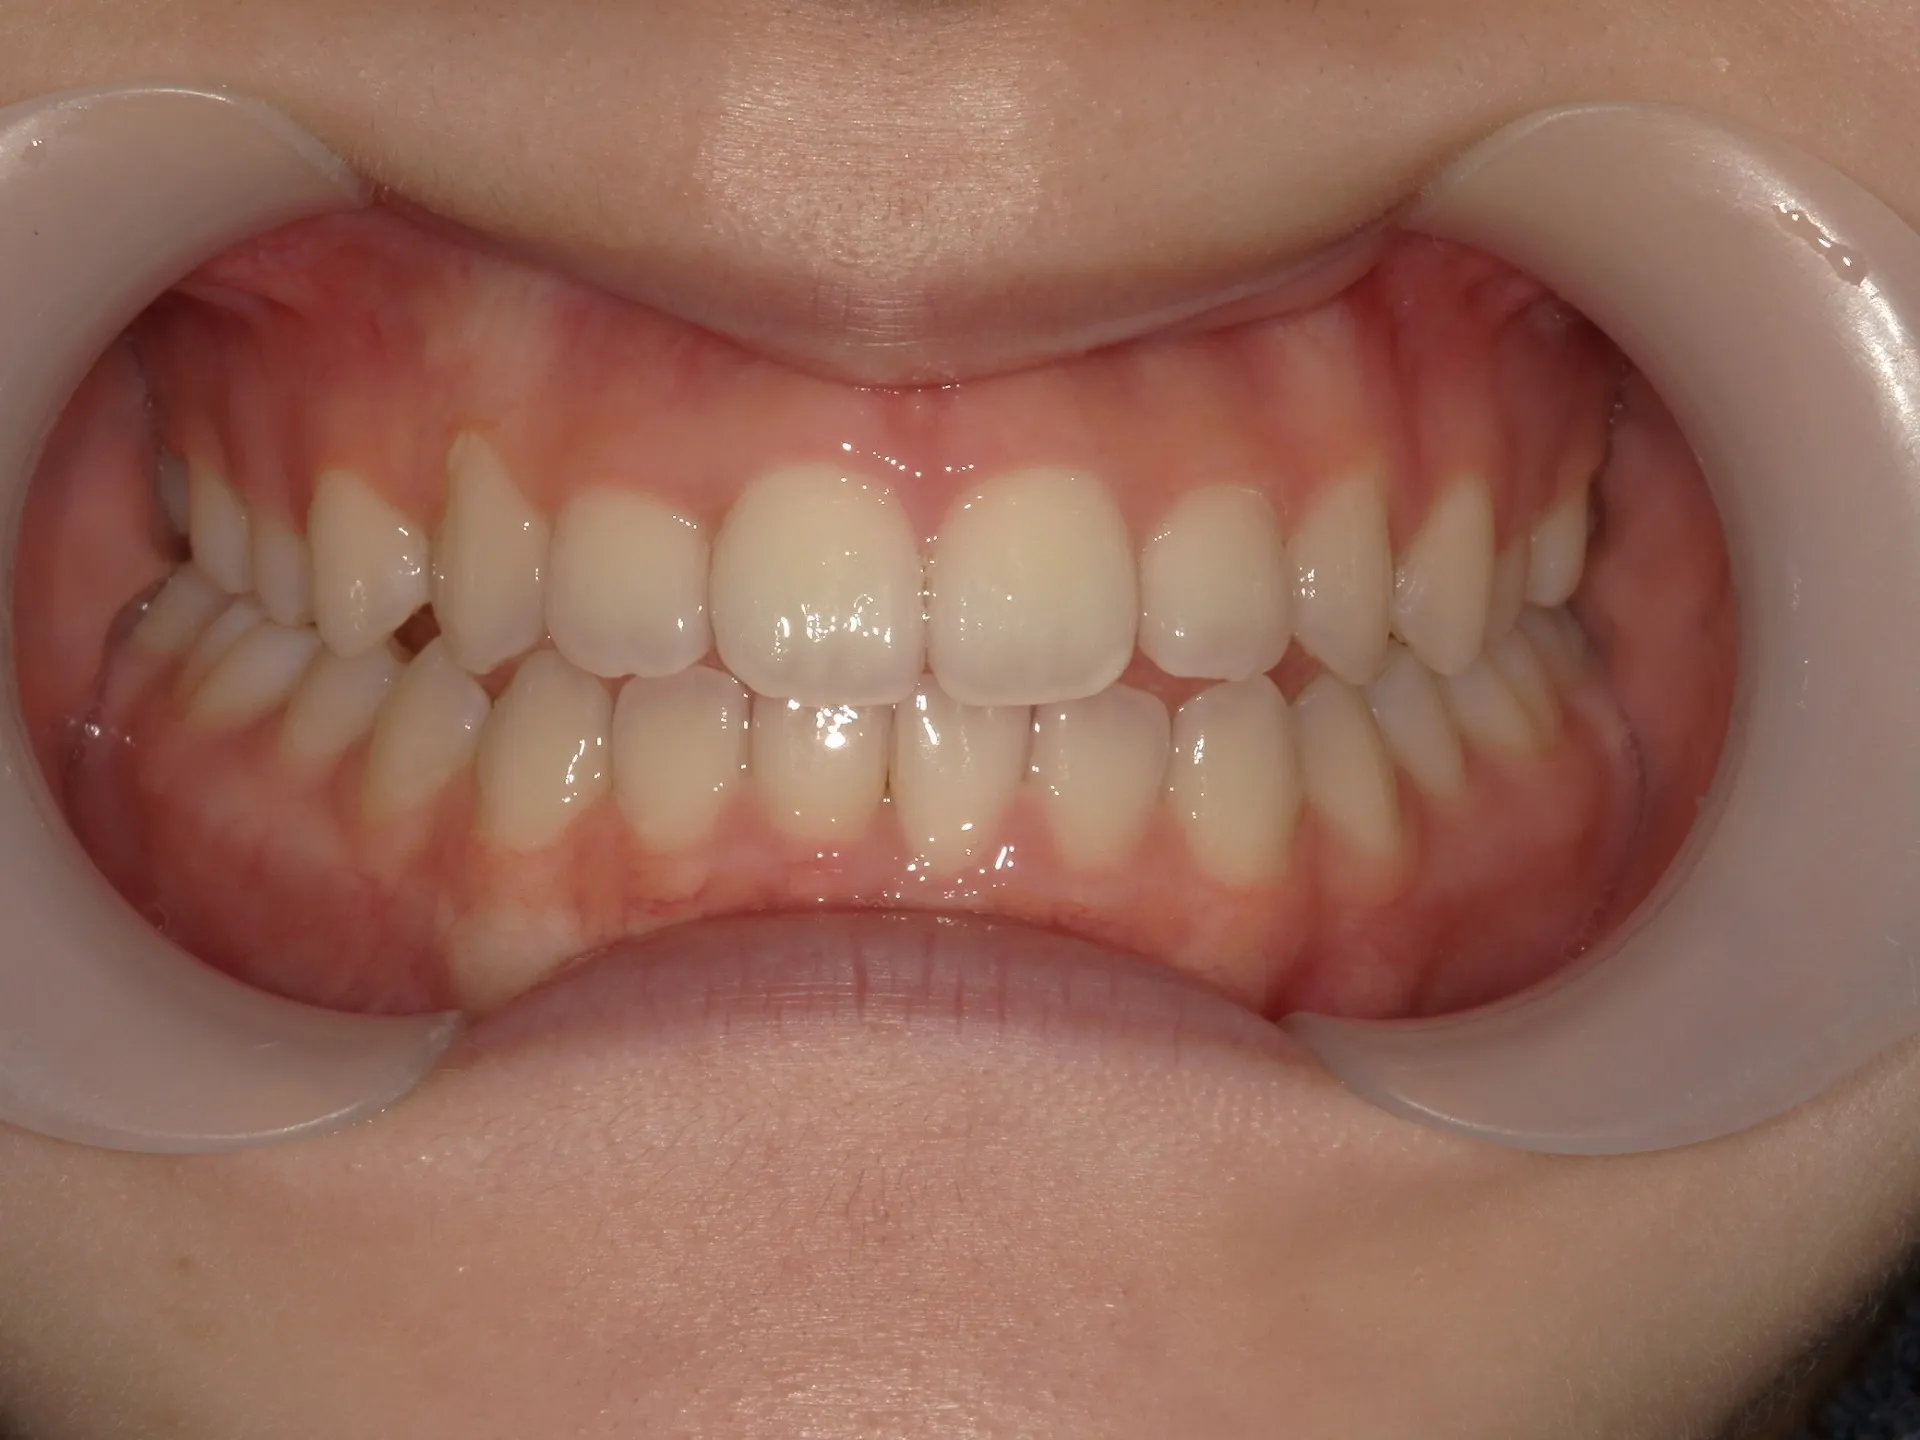

開咬治療後

正面観

治療後の正面観ですが、最初に見えていたスペースは大きく減少していることが分かりますが、左側にはややスペースは残存している状態です。

矯正治療では歯医者が目指すゴールと患者様が考えているゴールはしばしば異なることがあります。

今回は歯医者目線でお話するともう少し矯正を続けた方がよりきれいに機能的になると考えるため矯正治療の続行を提案したいところではあります。